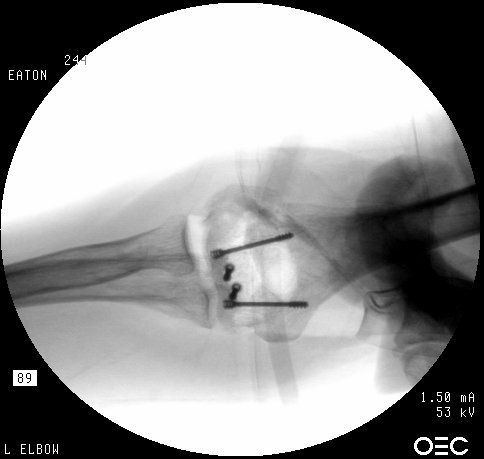

In similar steps, the reconstructed central articular component was secured to the proximal humerus with pins. Once satisfactory reduction was obtained (not yet, as seen here...), the pins were replaced by more Herbert screws. This allowed fixation of the purely osteochondral segments without prominent harware.

Screws were secured from the central articular component to the more proximal humeral cortices.

These provided biplanar fixation, eventually with two screws in each direction.

The lateral column was then secured with two cannulated screws.